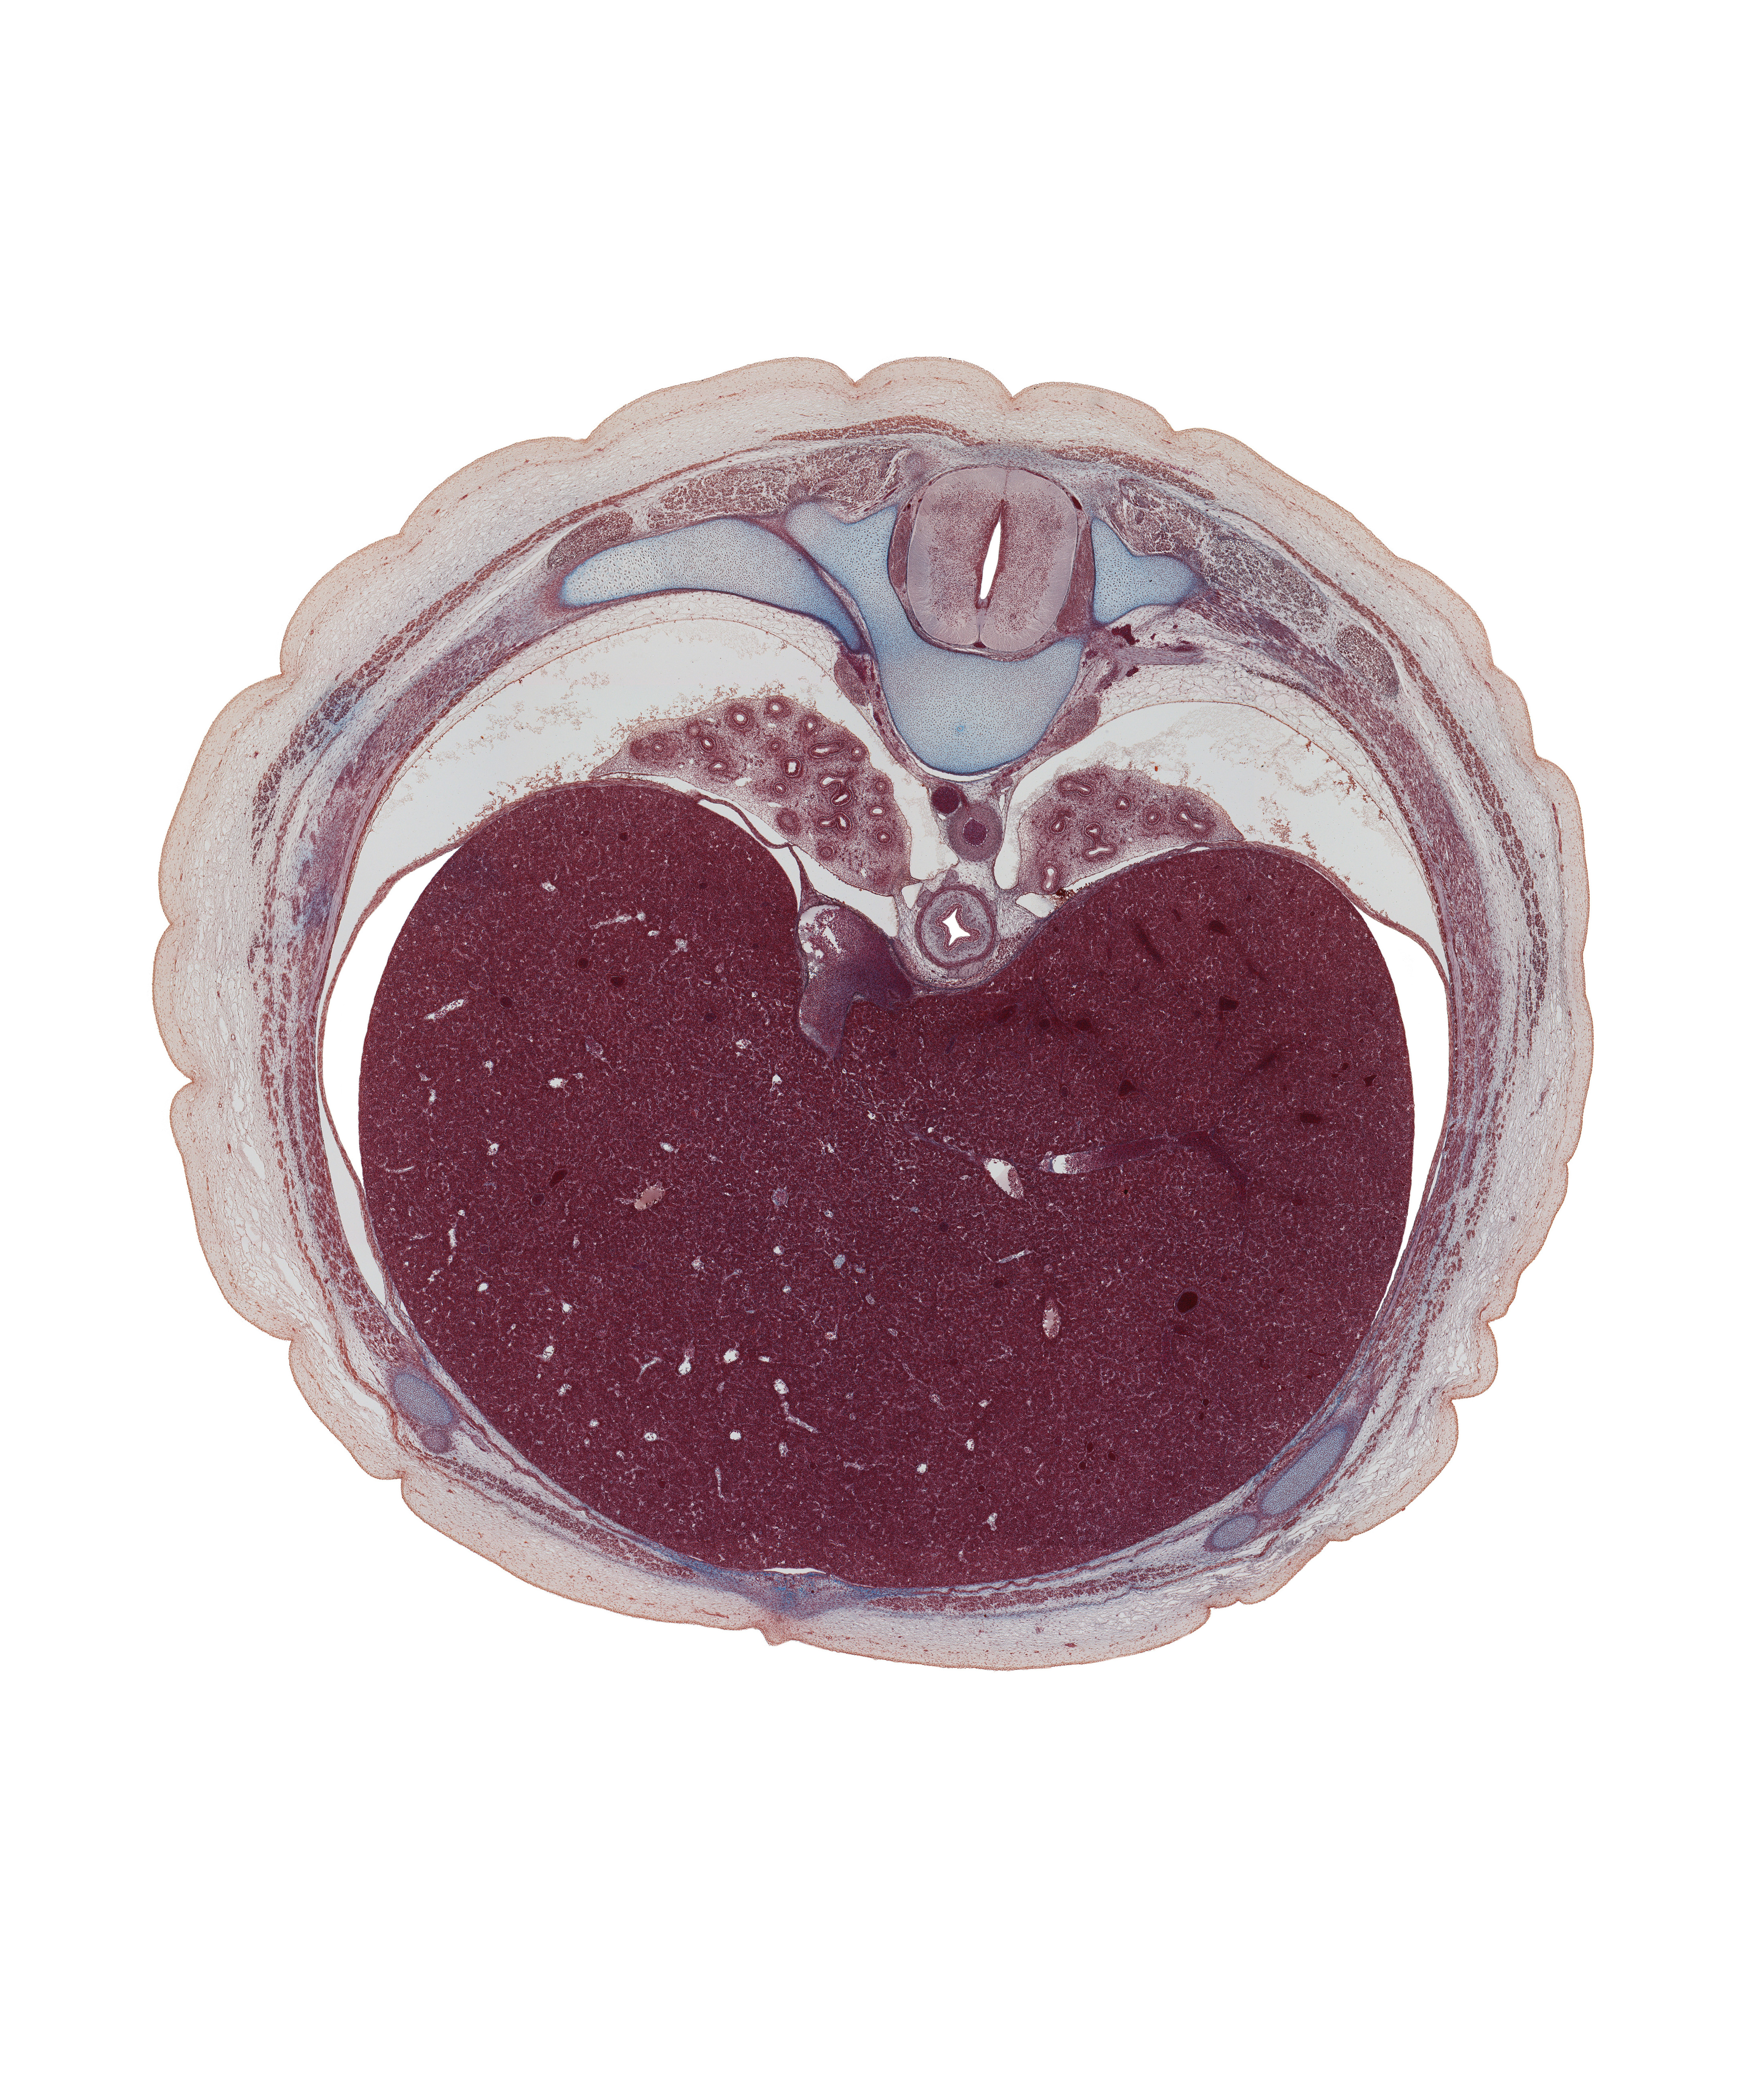

Carnegie Embryo #9226 | Location: 138-01-01

Keywords: T-8 spinal ganglion, anterior gastric nerve (CN X), anterior rectus sheath, common hepatic vein, costal margin, esophagus, external intercostal muscle(s), iliocostalis muscle, inferior vena cava, innermost intercostal muscle(s), internal intercostal muscle(s), left lobe of liver, longissimus muscle, posterior gastric nerve (CN X), pulmonary ligament, rectus abdominis muscle, right lobe of liver, spinalis muscle, transverse process, transversospinalis muscle, trapezius muscle, tributaries of left hepatic vein

Source: The Virtual Human Embryo.